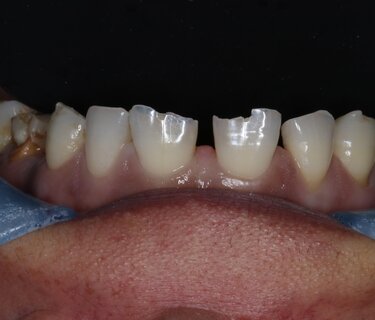

Figure 1: Blunt force trauma fractured and chipped this 19-year-old patient’s anterior teeth #7 and #8, which were repaired in single visit.

This case showcases how a trauma patient can be treated immediately in a single visit. This 19-year-old male presented to my practice with severely fractured teeth #7 and #8 (Figure 1) as a result of being assaulted. Unfortunately, he had waited 48 hours before seeking treatment and the exposed pulp required us to perform root canals on both anterior teeth with core buildups to retain the crowns (Figure 2).  The teeth were prepped and the preps scanned for import into CAD design software (ChairsideCAD, Exocad) (Figures 3 and 4). Two full-contour crowns in shade A2 (IPS e.max CAD, Ivoclar Vivadent) were milled, then crystalized, stained, glazed and placed in the mouth (Figure 5). One year later the patient returned for a post-op appointment to ensure the success of the root canal procedure and that the margins had filled in nicely with no inflammation (Figures 6 and 7).

Figure 2: Patient delay in seeking treatment resulted in root canals on both teeth being needed due to irreversible pulpitis.